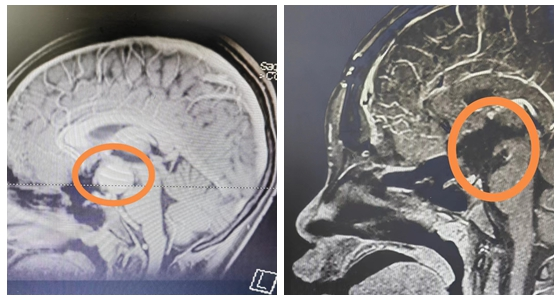

13岁的涵涵身高仅有145cm,体重37kg,比同班的男孩,甚至女孩都要矮小。起初,爸爸妈妈也没有太在意,以为孩子就是“长得晚”。2023年5月份开始,涵涵偶尔会跟爸爸妈妈说自己视物模糊,看不...